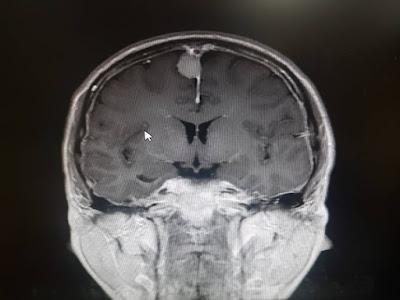

影像檢查

一個月後在神經內科做了MRA

1. 顱內低腦壓 intracranial hypotension

2. 腦膜瘤 menigioma 1cm